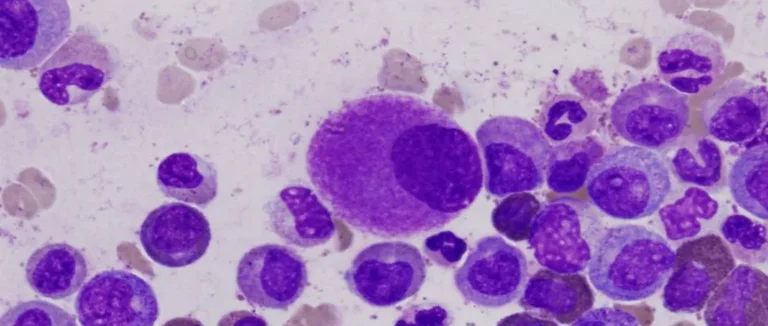

Chimiothérapie pour la leucémie myéloïde aiguë (LMA)

définir la leucémie lymphoblastique aiguë

diagnostic de la leucémie lymphoblastique aiguë